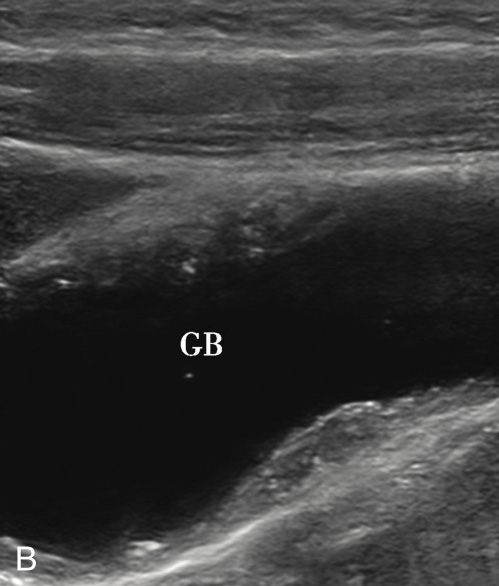

(1)局限型胆囊腺肌症:

好发于胆囊底部,灰阶超声图像通常呈边界清楚的低回声(图2-4-1A)。病变内部回声不均匀,能够观察到小片状无回声区,部分病变内可见点状高回声后伴彗星尾征(图2-4-1B)。CDFI通常无明显血流信号,部分病变内的点状高回声后方可见“快闪伪像”(图2-4-1C)。

图2-4-1 局限型胆囊腺肌症常规超声图像

A.胆囊底部低回声结节(箭头所示),边界清楚,形态规则;B.结节内可见点状高回声后伴彗星尾征(箭头所示);C.CDFI示结节内可见“快闪伪像”

GB:胆囊